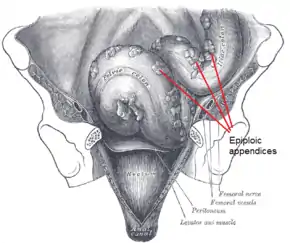

Epiploic appendages are also called appendices epiploicae. The appendages themselves are 50–100 appendages that are oriented in two rows anterior and posterior. The appendages are parallel to the superficial section of the taenia coli. Furthermore, the appendages are between 0.5 and 5 cm long, each appendage is attached with one or two arterioles and a venule within vascular stalks attached to the colon. Torsion (twisting or wrenching motion) of the appendages can cause ischemia which can cause painful symptoms that mimic other conditions such as diverticulitis, and appendicitis; however, it is rare. The pain associated with the inflamed appendages is located in the left and sometimes in the right lower abdominal quadrant. Diagnosis of epiploic appendagitis can be challenging due to its infrequency.[5]